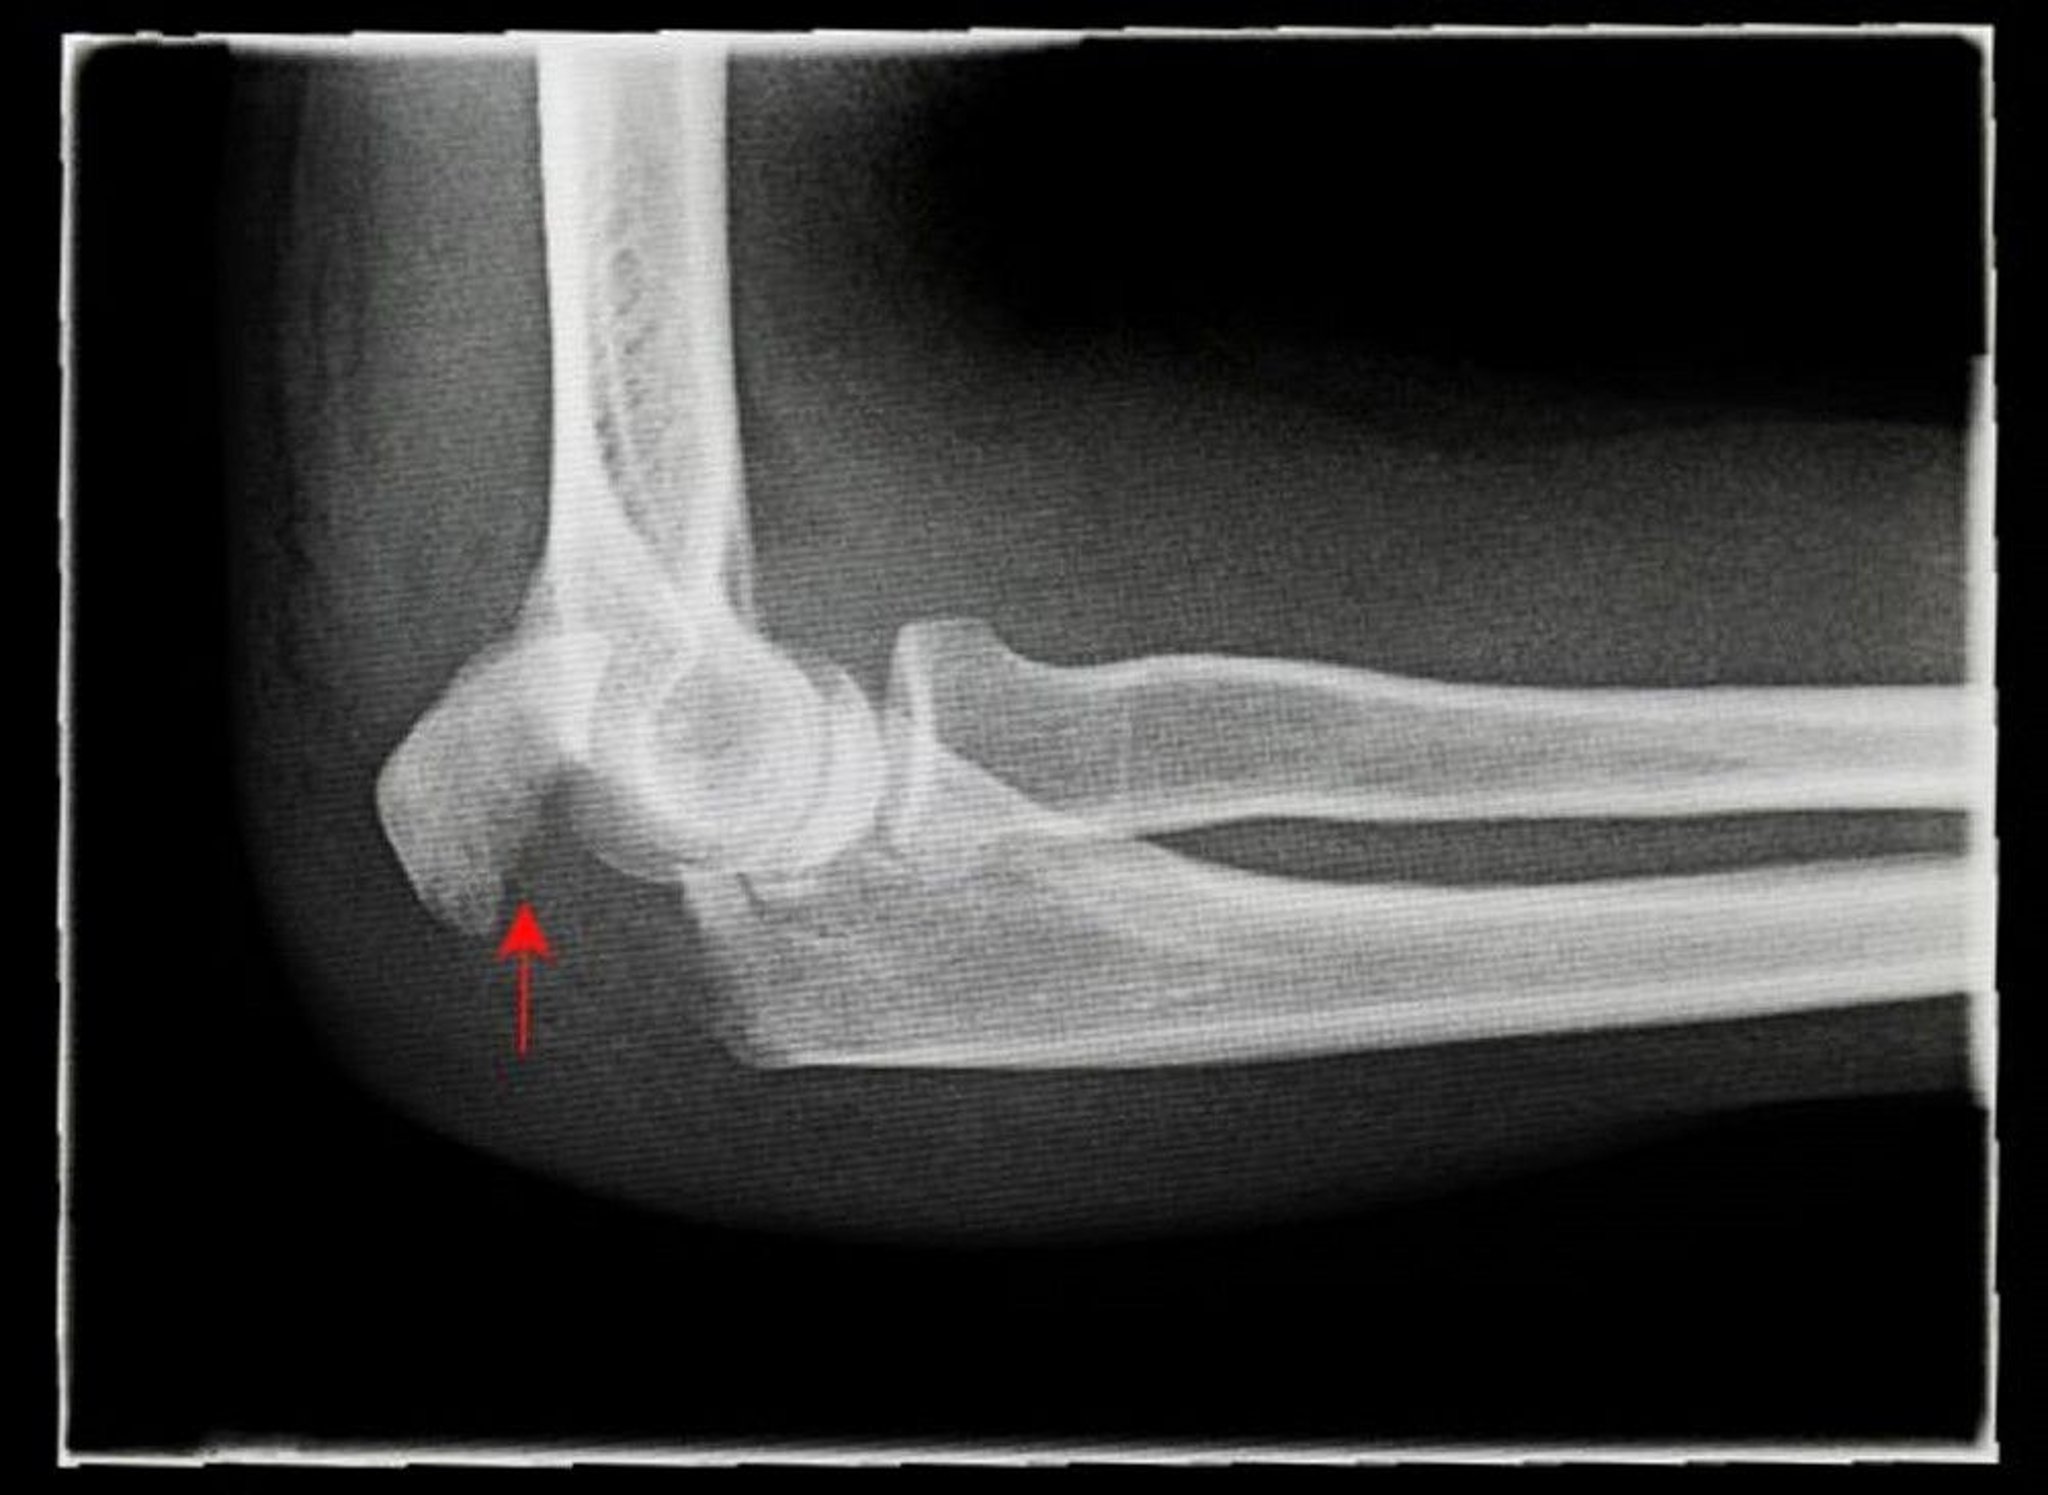

Displaced Olecranon Fracture

This x-ray shows a side (lateral) view of a displaced olecranon fracture (arrow).